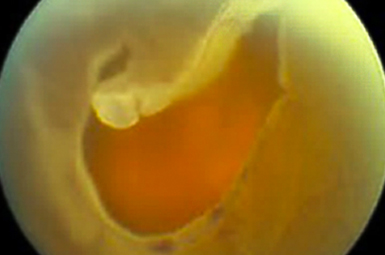

Macular Hole

A Macular Hole creates a blank space in the central “film of your camera”. Surgical repair is typically highly successful.

Image courtesy of Carl Zeiss Meditec, Inc.